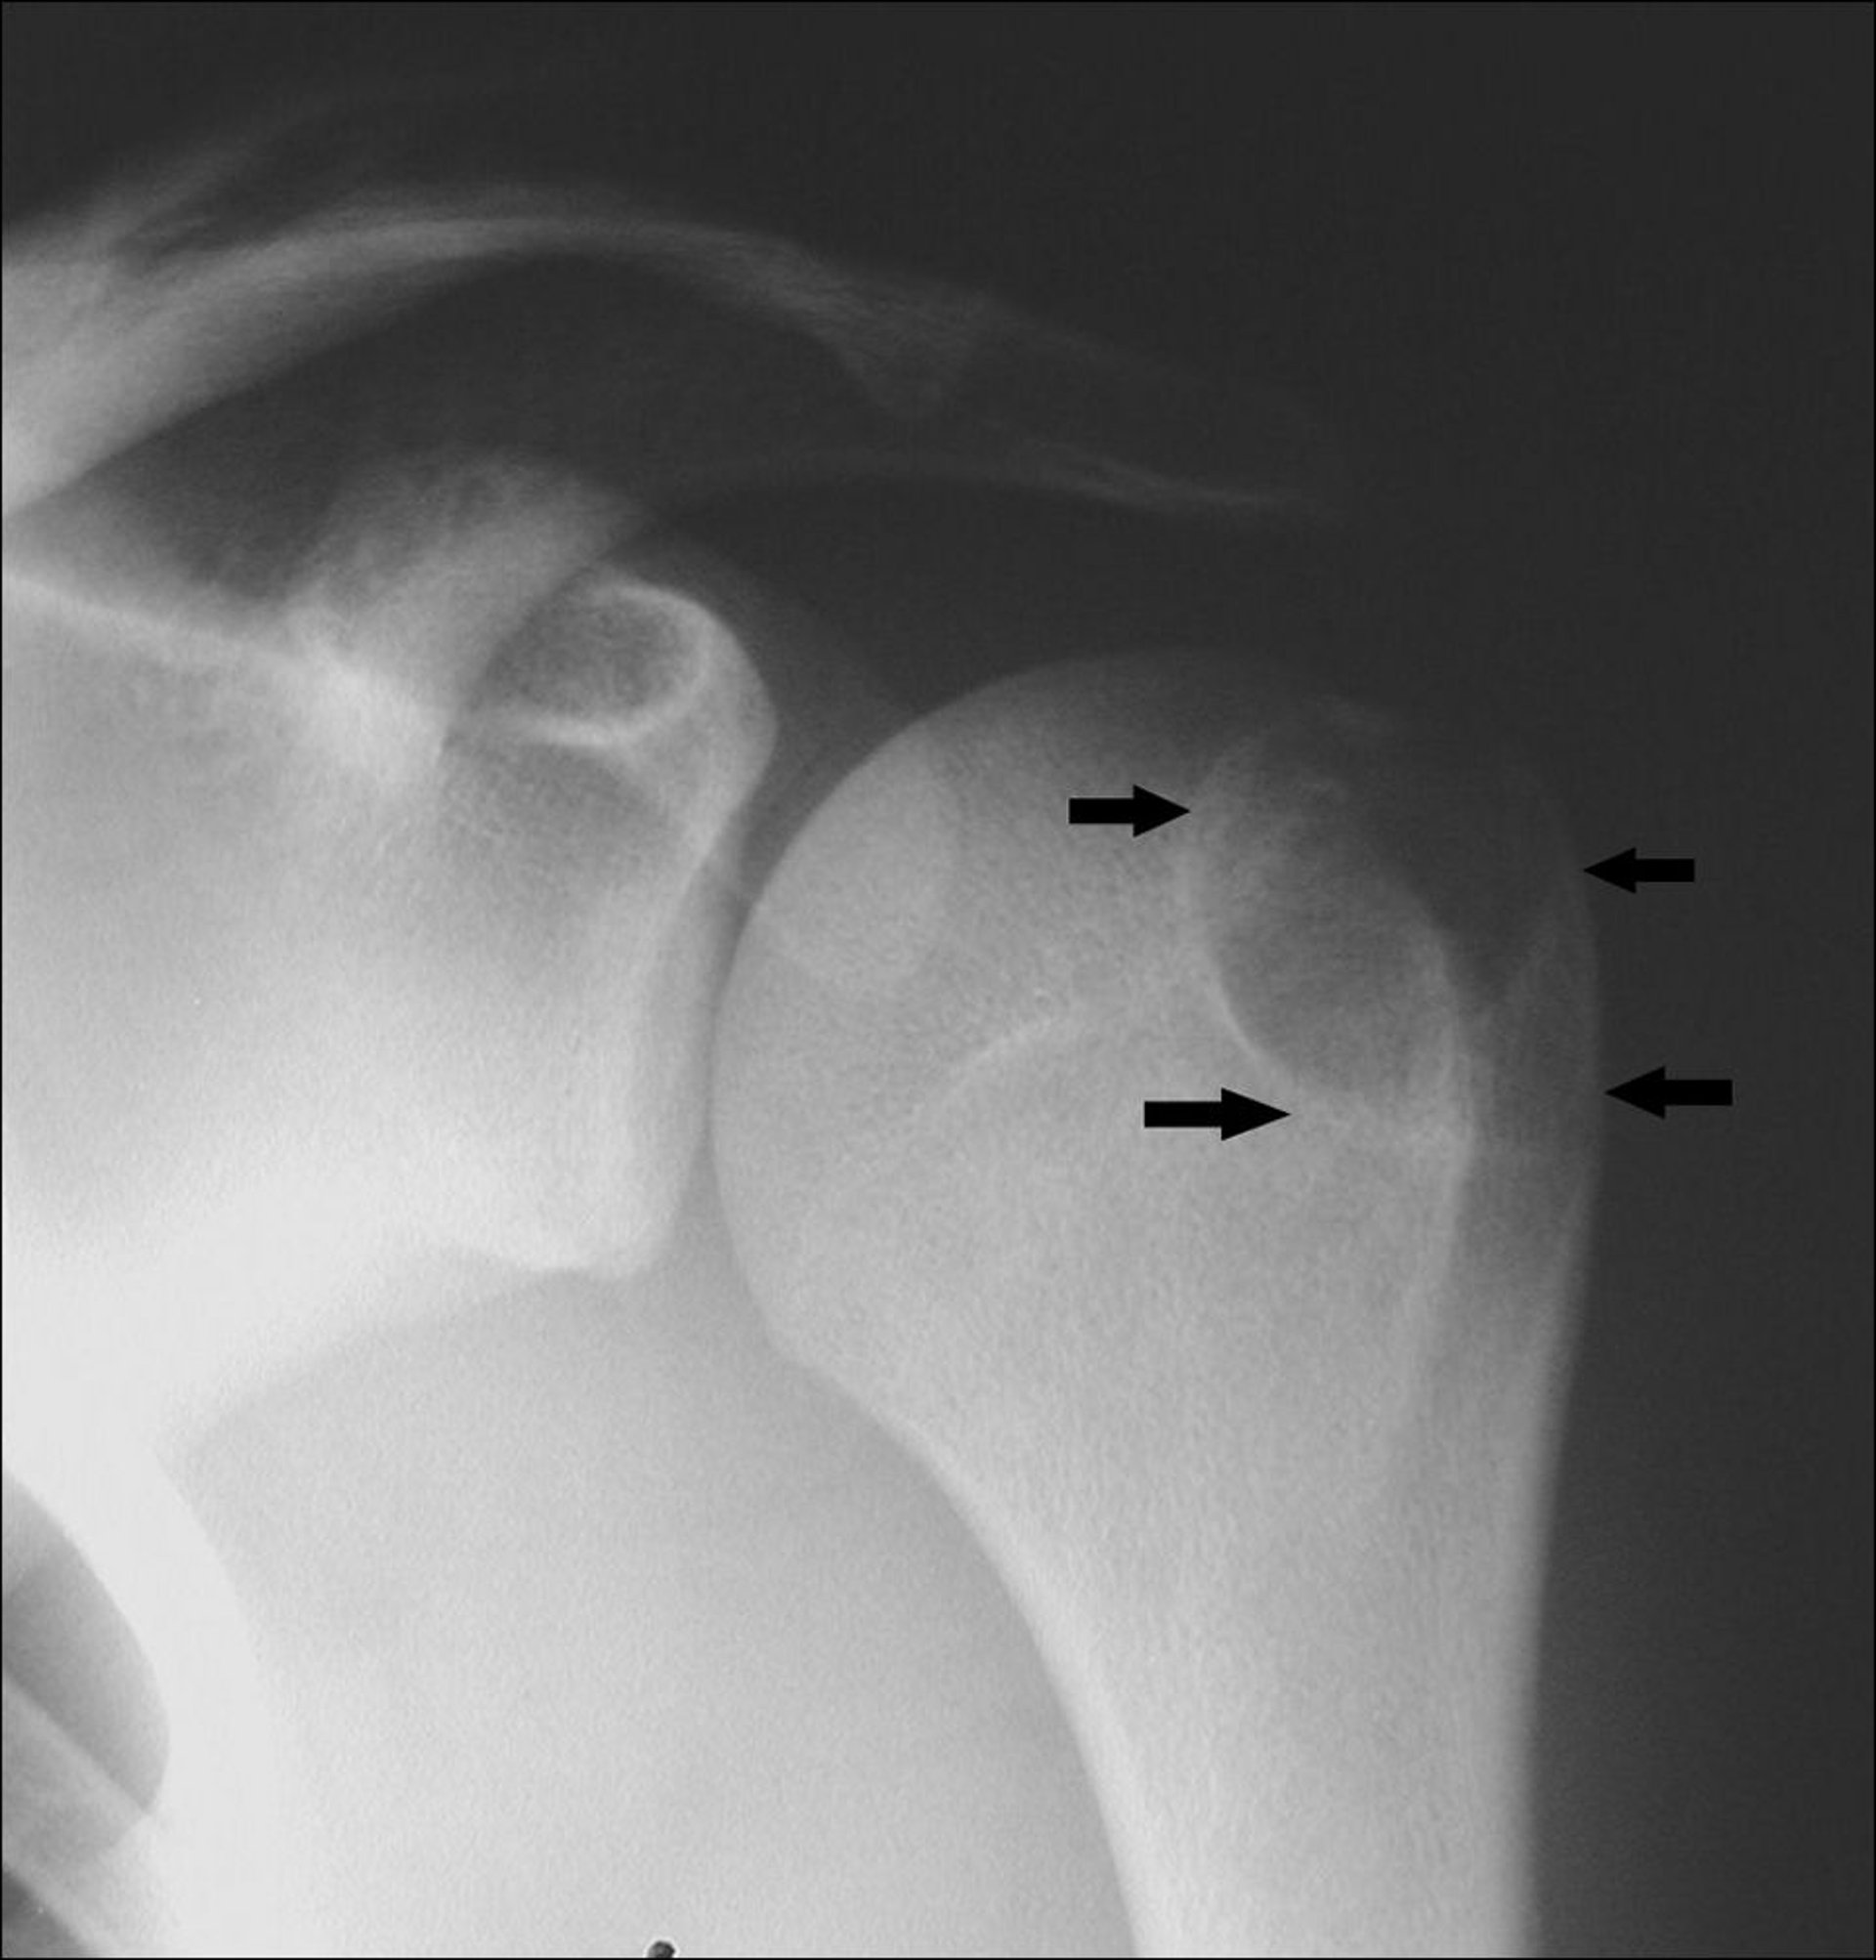

Esta radiografía de hombro muestra un condroblastoma en el húmero en la tuberosidad de mayor tamaño (flechas).

Image courtesy of Michael J. Joyce, MD, and Hakan Ilaslan, MD.